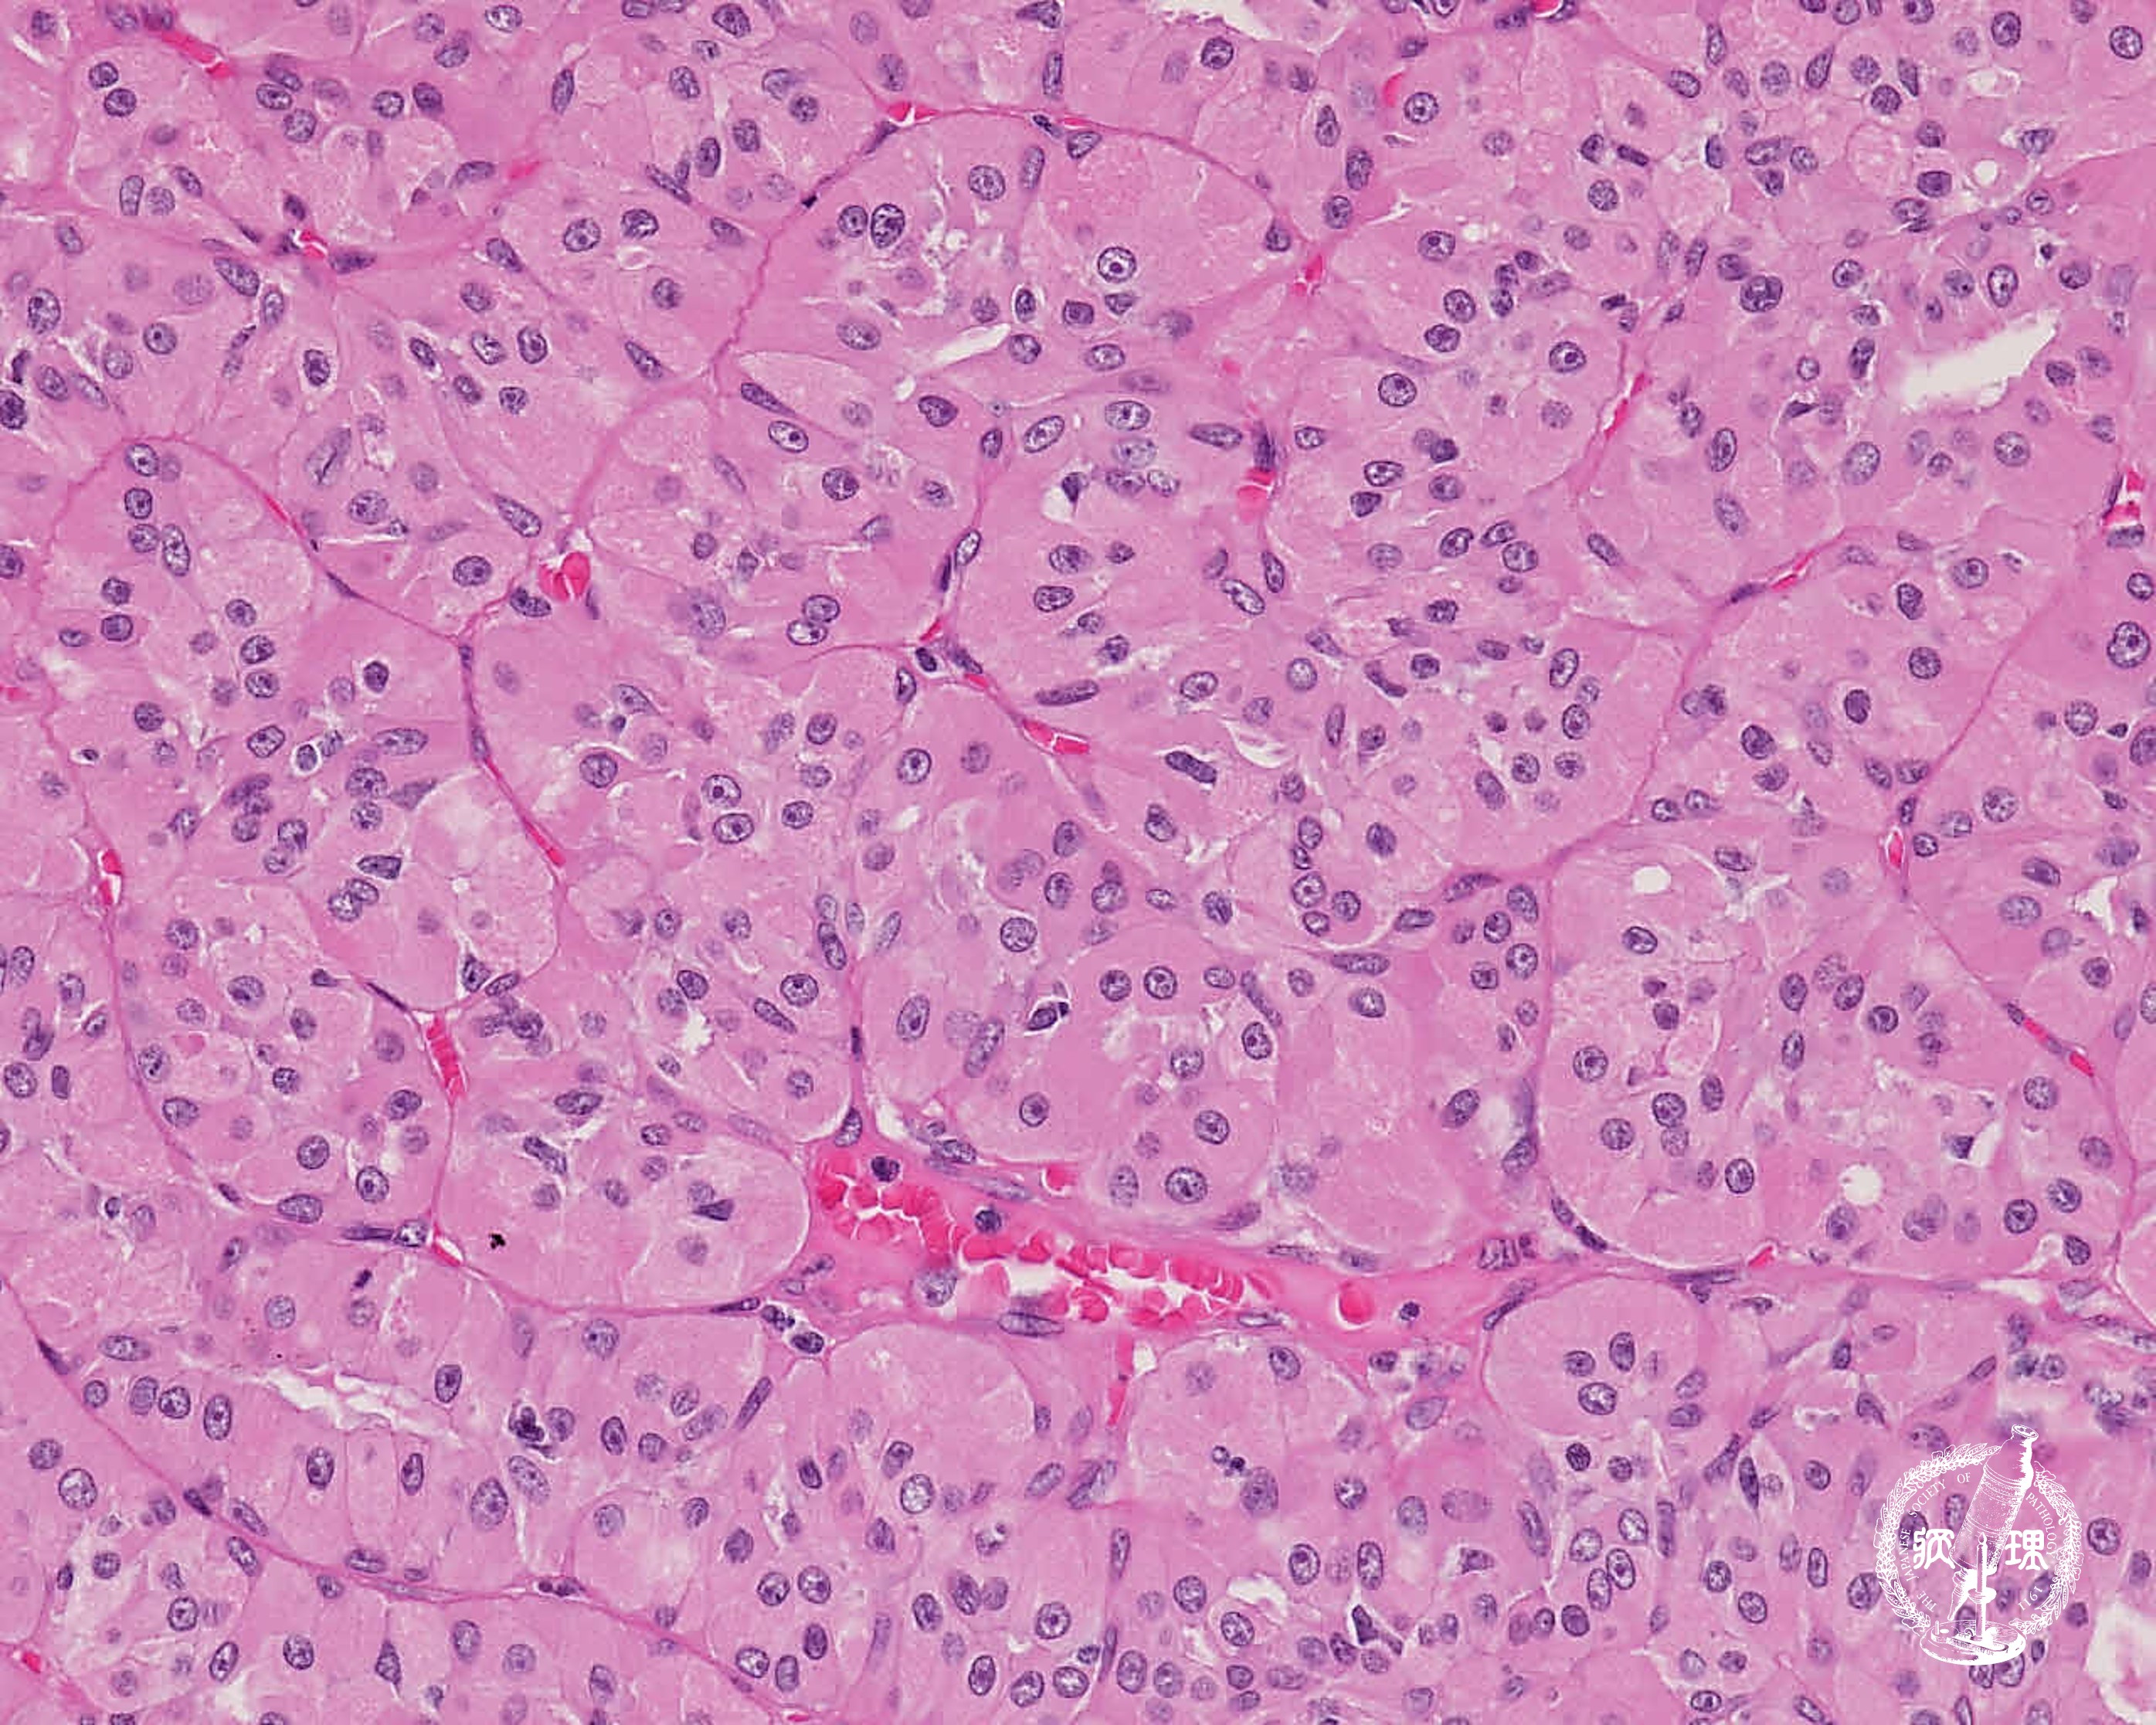

• 唾液腺腫瘍 (オンコサイトーマ)